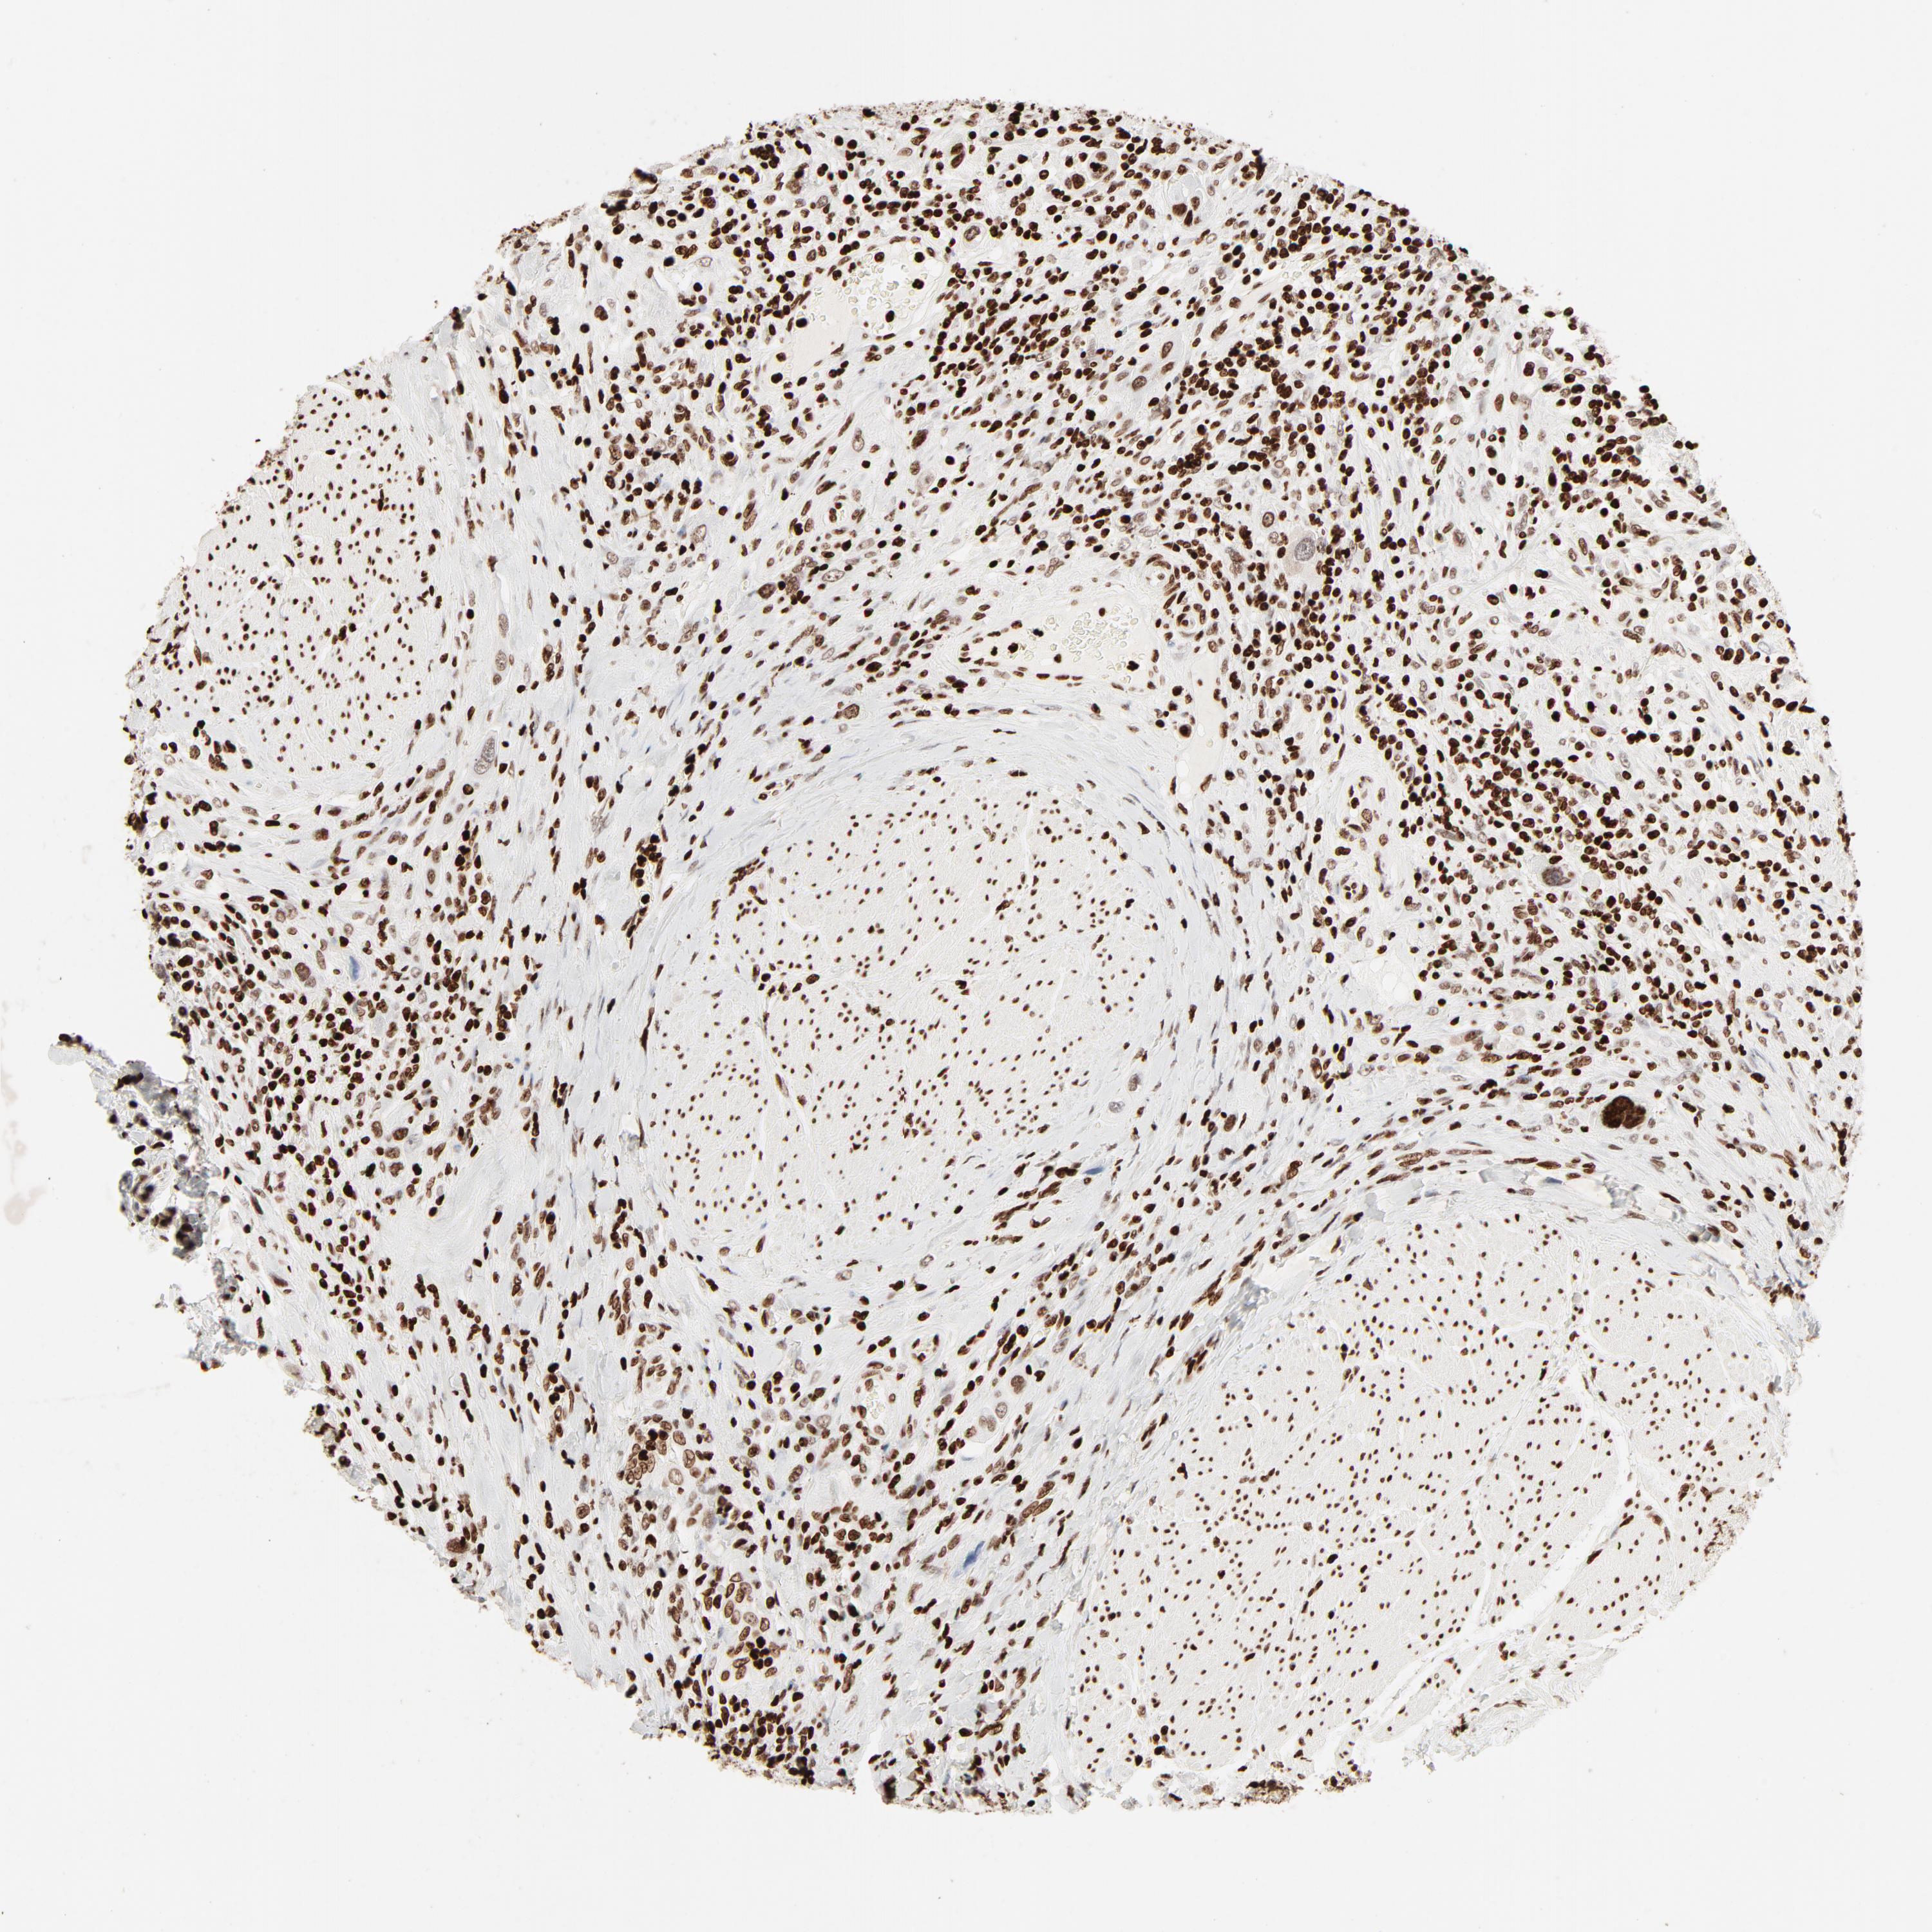

UROTHELIAL CANCER - Protein expressioni

A mouse-over function shows sample information and annotation data. Click on an image to view it in a full screen mode. Samples can be filtered based on level of antibody staining by selecting one or several of the following categories: high, medium, low and not detected. The assay and annotation is described here.

Note that samples used for immunohistochemistry by the Human Protein Atlas do not correspond to samples in the TCGA dataset.

Antibody stainingi

Antibody staining in the annotated cell types in the current human tissue is reported as not detected, low, medium, or high, based on conventional immunohistochemistry profiling in selected tissues. This score is based on the combination of the staining intensity and fraction of stained cells.

Each image is clickable and will lead to virtual microscopy that enables deeper exploration of all samples and also displays staining intensity scores, fraction scores and subcellular localization as well as patient and tissue information for each sample.

Antibody HPA003506

Antibody CAB005873

Staining

High

Medium

Low

Not detected

Intensity

Strong

Moderate

Weak

Negative

Quantity

>75%

75%-25%

<25%

None

Location

Nuclear

Cytoplasmic/membranous

Cytoplasmic/membranous,nuclear

Urothelial carcinoma, High grade

Urothelial carcinoma, Low grade